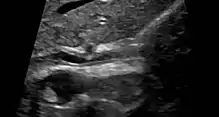

| Cholangiogram of primary sclerosing cholangitis | |

Historically, a cholangiogram would be obtained via endoscopic retrograde cholangiopancreatography (ERCP), which typically reveals "beading" (alternating strictures and dilation) of the bile ducts inside and/or outside the liver. Currently, the preferred option for diagnostic cholangiography, given its noninvasive yet highly accurate nature, is magnetic resonance cholangiopancreatography (MRCP), a magnetic resonance imaging technique. MRCP has unique strengths, including high spatial resolution, and can even be used to visualize the biliary tract of small animal models of PSC.[21]